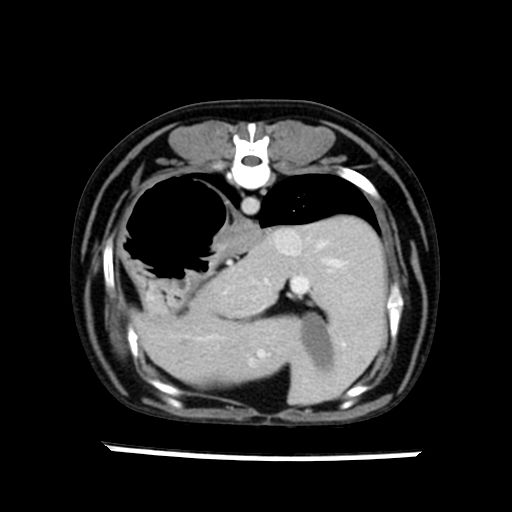

prescritto esame TAC

sequenza immagini limitata al fegato reni e surreni

le immagini ecografiche rispetto alla tac datano circa 7 mesi prima ,le surrenali sono normali nonostante il test acth sia risultato positivo .all’esame TAC dopo diversi mesi risultano aumentate armonicamente nel volume e si individua un forte sospetto di adenoma ipofisario .

sospetto adenoma ipofisario vs. meno probabilmente meningioma della base; intertiziopatia polmonare; lesione espansiva epatica, verosimilmente del lobo laterale sinistro, di sospetta natura neoplastica; lesioni spleniche di natura da definire; iperplasia/ipertrofia delle ghiandole surrenali, bilateralmente; vertebra di transizione del rachide toracico; tenosinovite cronica del muscolo bicipite brachiale di destra.

- Nessuna informazione diversa per quello che riguarda l’esame ecografico del fegato e la presa del contrasto si confermano le lesioni individuate e l’ipoenanchement in fase portale.

- la total body permette di escludere metastasi e di avvicinarsi all’interventistica